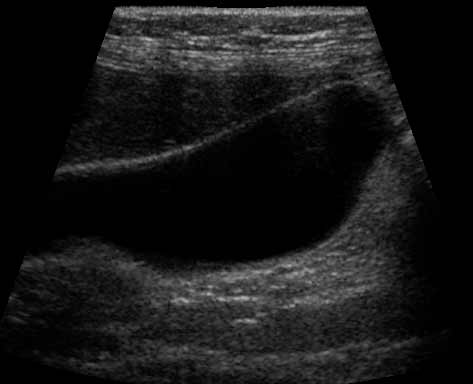

Ultrasound of the gallbladder. The wall or lining of the gallbladder is white, the bile within the gallbladder is mostly made of water and it appears as a clear black space within the walls of the gallbladder.

Note: Images are shown for illustrative purposes. Do not attempt to draw conclusions or make diagnoses by comparing these images to other medical images, particularly your own. Only qualified physicians should interpret images; the radiologist is the physician expert trained in medical imaging.